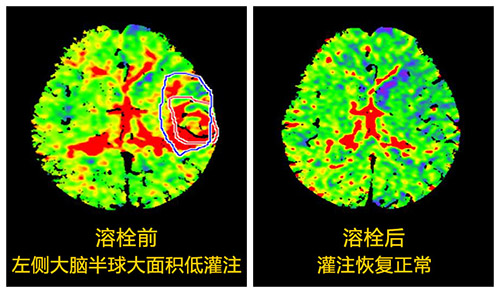

张静波听完电话直奔医院,同时她用手机指挥临床一线医生进行应急处理。随后张主任对患者进行了多模式CT评估,判断他的条件已符合溶栓治疗,再加上自己多年的溶栓经验,她决定对其进行溶栓治疗。经过一个多小时的精心溶栓,患者的上肢和下肢竟奇迹般的动了起来,他终于脱离了生命危险,家属因此非常感激。

“这是我进行超时间窗急性脑梗死溶栓治疗的患者之一,也是溶栓时间比较长的一个,虽然满足溶栓的要求,可他毕竟已错过溶栓的黄金时间窗,心理还是有些紧张。但患者当时情况危急,如不及时治疗,他一侧身体就会偏瘫、麻木,还会失语,严重时将会危及生命,为了挽救患者,我愿倾尽全力。”,张主任说,“之后患者把我推荐给他的朋友、邻居、同事,并说有类似的病一定要来找我,直到现在还会隔三差五打电话,早就成了老朋友。”

▲张静波CT指导扩大时间窗溶栓案例引媒体纷纷报道

2007年张静波师从全国神经科的领军人物——北京天坛医院院长王拥军教授,他是国家最早“十一五”研究项目的领头人,她跟随王拥军教授学习并参与其研究项目。经过自身的艰苦奋斗以及团队的精诚合作,终于在2007年她在国内率先开展了《多模式CT指导的扩大时间窗急性脑梗死溶栓治疗》研究,并在中华神经科杂志率先发表,填补了国内空白,该论文2013年获中华神经科杂志优秀论文三等奖。共发表论文20余篇,其中SCI一篇;主编著作1部,参编著作3部,大连市科技进步二等奖一项;辽宁省科技进步三等奖一项。自2007年承担国家“十一五”课题协作项目、国家新药平台、卫生行业科研专项、“十二五”、“十三五”等多项研究课题,都取得了瞩目的成就,并获科研经费150余万元。